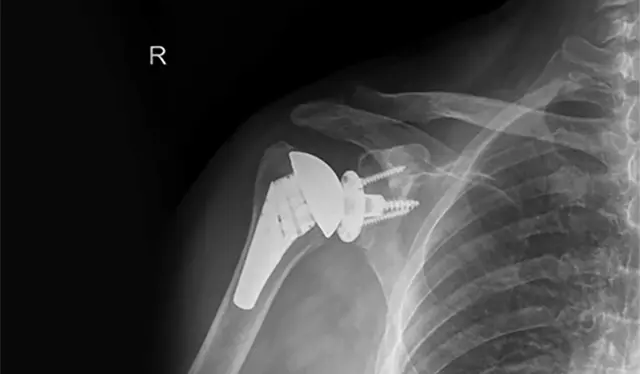

Ο ιατρός είναι κορυφαίος Διευθυντής Ορθοπαιδικός Χειρουργός. Eξειδικεύεται στην αρθροσκοπική και επανορθωτική χειρουργική του ώμου και του άνω άκρου όπου είναι κορυφή στον τομέα του.

Το πεδίο εξειδίκευσης του γιατρού περιλαμβάνει τις πιο σύγχρονες χειρουργικές τεχνικές

EXCELLENT Based on 289 reviews Posted on Panos LoukasTrustindex verifies that the original source of the review is Google. Η επέμβαση που έκανα στον ώμο ήταν επιτυχημένη, ο γιατρός πολύ επεξηγηματικός και υποστηρικτικός και πάντα διαθέσιμος!Posted on Σάββας ΚοτρικηςTrustindex verifies that the original source of the review is Google. Ευχαριστώ πολύ τον γιατρό Ιωάννη Πολυζωη γιατί μετά από ένα δύσκολο χειρουργείο ολικής αρθροπλαστικης ώμου, είμαι σε άριστη κατάσταση.Posted on Eleni RizouTrustindex verifies that the original source of the review is Google. Υποβλήθηκα σε αρθροσκόπηση ώμου από τον κ. Πολυζώη και η εμπειρία ξεπέρασε κάθε προσδοκία. Πρόκειται για έναν εξαιρετικό χειρουργό, με κορυφαία επιστημονική κατάρτιση. Από την πρώτη στιγμή με αντιμετώπισε με σεβασμό, ειλικρίνεια και πραγματικό ενδιαφέρον, εξηγώντας με σαφήνεια όλες τις λεπτομέρειες της πάθησης και της επέμβασης. Η αρθροσκόπηση πραγματοποιήθηκε με απόλυτη επιτυχία, χωρίς καμία επιπλοκή, και η ανάρρωση ήταν εντυπωσιακά γρήγορη. Τον συστήνω ανεπιφύλακτα ως έναν από τους καλύτερους ορθοπεδικούς χειρουργούς με κορυφαία κατάρτιση και εμπειρία.Posted on Marianna AggelakiTrustindex verifies that the original source of the review is Google. Καταπληκτικός γιατρός,εξαιρετικός άνθρωπος . Προσιτός στον ασθενή με φοβερές γνώσεις και εμπειρία.Απο προσωπική εμπειρία πριν λίγες μέρες με σοβαρό πρόβλημα στον ώμο μου η αντιμετώπιση ήταν άμεση και το αποτέλεσμα της αποκατάστασης πολύ γρήγορο. Ευχαριστώ πολύ κ.Πολυζωη!!!!!Posted on DT TseTrustindex verifies that the original source of the review is Google. Εξαιρετικός ορθοπεδικός χειρουργός! Έπαθα ρίξη στους τέντοντες του αριστερού ώμου και τότε μου συνέστησαν τον Δρ. Ιωάννη Πολυζώη. Έπειτα απο τις απαραίτητες εξετάσεις και αφού μου εξήγησε τι ακριβώς πρέπει να γίνει, υποβλήθηκα σε αρθροσκόπηση με συρραφή των τενόντων και η εμπειρία μου ήταν άψογη από την αρχή μέχρι το τέλος. Ο Δρ. Ιωάννης Πολυζώης, Χειρούργος Ορθοπεδικός, έδειξε επαγγελματισμό, ανθρωπιά και πραγματικό ενδιαφέρον για την αποκατάστασή μου. Μου εξήγησε αναλυτικά την διαδικασία, με έκανε να αισθανθώ ασφαλής και το αποτέλεσμα του χειρουργείου ήταν εξαιρετικό. Η αποθεραπεία κύλησε ομαλά χάρη στις σαφείς οδηγίες του και την άμεση ανταπόκριση σε κάθε μου απορία. Είχε πάντα συνεχή επικοινωνία μαζί μου αλλά και με τον φυσιοθεραπευτή μου, για την καλύτερη προσέγγιση στην αποκατάστασή μου. Αξίζει επίσης να αναφέρω πως το ιατρείο του είναι υπερσύγχρονο και πλήρως εξοπλισμένο. Από την πρώτη στιγμή ένιωσα ότι βρίσκομαι σε καλά χέρια, σε ένα περιβάλλον που εμπνέει εμπιστοσύνη και επαγγελματισμό. Τον συνιστώ ανεπιφύλακτα σε όποιον αναζητά έναν αξιόπιστο και έμπειρο χειρούργο ορθοπεδικό!Posted on Stefanos TogoussidisTrustindex verifies that the original source of the review is Google. Εξαιρετικός ως επιστημών και ως άνθρωπος . Είχα απόλυτη επιτυχία στην άρθρο πλαστική ωμού και νιώθω τέλεια Νομίζω ότι ο κ. Πολυζώης θα πρέπει είναι σημείο αναφοράς Ένα τόνο μετά την πρώτη αναστροφή ολική Άρθρο πλαστική στον αριστερό μου ώμο πήρα απόφαση να κάνω και στον δεξί μου ώμο το ίδιο . Πήγα στον κ Πολυζώη τον εξαιρετικό γιατρό επιστήμονα αλλά πάνω από όλα άνθρωπο να αναλάβει το δύσκολο αυτό έργο με δεδομένο ότι ο ώμος μου είχε και μια κλήση που έκανε τα πράγματα πολύ πιο δύσκολα. Το αποτέλεσμα όπως αναμένονταν εξαιρετικό. Λίγες εβδομάδες μετά ο ώμος μου είναι σε εξαιρετική κατάσταση. Χάρι στον κ Ι Πολυζώη έχω 2 ώμους σε τέλεια κατάσταση χωρίς πόνους και λειτουργικούς. Πραγματικά ότι και να πεις για τον Ι Πολυζώη τον επιστήμονα τον γιατρό τον άνθρωπο που σε βλέπει σαν α είσαι φίλος του από πάλαια και θέλει να προσφέρει όλες τις γνώσεις του κσι την εμπειρία του για να σε βοηθήσει του αξίζει ένα μεγάλο ευχαριστώ να είναι πάντα καλά. Τέλος θα πω κάτι που πραγματικά πιστεύω πρέπει να γίνει το σημείο αναφοράς όσον αφορά τους ώμους και άνω άκρα Μακάρι να είχαμε και άλλους σαν τον Ι Πολυζώη θα νοιθωθαμε όλοι ασφάλεια και σιγουριά εγώ σε ευχαριστώ πολυ από τα βάθη της καρδιάς μου !!Posted on Σωτήρης ΓκούνηςTrustindex verifies that the original source of the review is Google. Φιλικος και καταρτισμενος γιατρος!Posted on Gabriele PinzoneTrustindex verifies that the original source of the review is Google. We are very happy to have chosen Dr. Polyzois for a problem at the leg of my wife: he is very professional but he was also very friendly and helpful since the very first phone call. As Expats just relocated in Greece we have even more appreciate these qualities along with his excellent English!Posted on Stathis TsamtsourisTrustindex verifies that the original source of the review is Google. Εξαιρετικός γιατρός πραγματοποίησε άψογη εκτέλεση εργασίας σε σοβαρό πρόβλημα στο ώμο σου εμπνέει εμπιστοσύνη και σαν γιατρός και σαν άνθρωποςPosted on Eleni KourtTrustindex verifies that the original source of the review is Google. Είχα την τύχη να επισκεφθώ τον κ. Πολυζώη για ένα ορθοπεδικό πρόβλημα που με ταλαιπωρούσε και πραγματικά έμεινα εντυπωσιασμένη από το επίπεδο επαγγελματισμού του. Από την πρώτη στιγμή έδειξε προσοχή, ευγένεια και διάθεση να ακούσει προσεκτικά τα συμπτώματά μου. Η εξέταση ήταν λεπτομερής και κατανοητή, με σαφείς εξηγήσεις για την αιτία του προβλήματος και τις διαθέσιμες επιλογές θεραπείας. Με έκανε να αισθανθώ σιγουριά και εμπιστοσύνη, καθώς φαινόταν ξεκάθαρα ότι γνωρίζει σε βάθος το αντικείμενο του. Όσες φορές κι αν τον κάλεσα, όσες φορές κι αν χρειάστηκε να τον επισκεφθώ ή να ζητήσω βοήθεια, ήταν πάντα πρόθυμος και διαθέσιμος να με εξυπηρετήσει. Με υπομονή και επαγγελματισμό μου εξηγούσε κάθε λεπτομέρεια, ώστε να καταλαβαίνω ακριβώς τι συμβαίνει και πώς θα προχωρήσουμε. Η επικοινωνία ήταν άψογη, η φροντίδα ανθρώπινη και η αντιμετώπιση εξατομικευμένη, προσαρμοσμένη στις ανάγκες μου. Τον συστήνω ανεπιφύλακτα σε όποιον αναζητά έναν εξαιρετικό γιατρό με επιστημονική κατάρτιση, επαγγελματική συνέπεια και πραγματικό ενδιαφέρον για τον ασθενή.